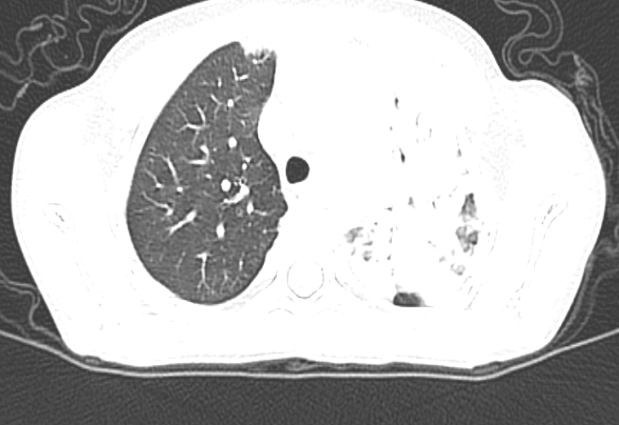

儿科二区近期收治了1名 7 岁的患儿,因 “反复发热伴咳嗽 4 天” 前往申冬冬副主任医师门诊就诊。初步完善胸部彩超后,提示患儿存在肺实变,病情较重,遂紧急收治入院。入院后,乔淑楠主治医师结合患儿症状、体征及彩超结果,判断肺部感染情况复杂,建议进一步完善胸部 CT 及呼吸道病原学检查。检查结果证实:患儿左肺上叶炎症伴部分实变,且存在肺炎支原体阳性,凝血功能异常;更危险的是,患儿左上肺出现大面积肺不张。

经过全科医护人员的精心治疗与护理,患儿病情逐步好转,复查胸部 CT 显示左肺上叶炎症明显吸收,肺不张情况得到显著改善,目前已顺利康复出院,赢得了家属的高度赞誉。